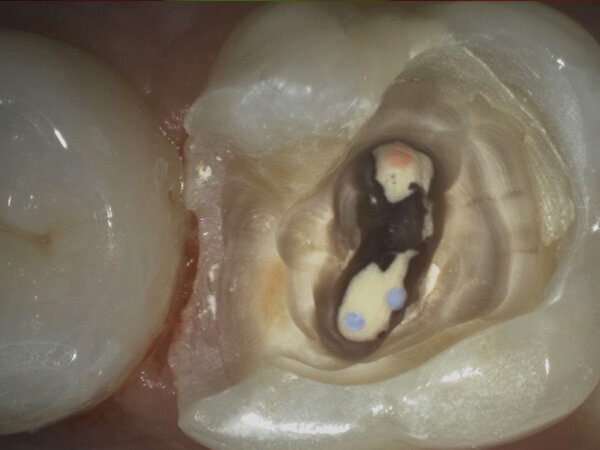

- Rilevamento precoce di patologia orale - La diagnosi precoce è un imperativo cui il dentista deve attenersi per garantire trattamenti meno invasivi, costosi e rapidi. L’illuminazione coassiale, la possibilità di elevato ingrandimento, la facilità di esplorazione di aree di difficile accesso aumentano l’efficacia diagnostica e rendono la telecamera uno strumento insuperabile tanto per l’osservazione della mucosa orale quanto per l’individuazione di concrezioni di tartaro o soluzioni di continuità nei tessuti dentali e nei margini dei restauri.

- Relazione paziente-medico migliorata - Il vantaggio più peculiare è la grande capacità di coinvolgimento del paziente nel processo di diagnosi e cura, condizione auspicabile affinché quanto proposto sia avvertito come attendibile. La relazione paziente-medico può risultare critica quando manchi la chiara comprensione della patologia di cui si è afflitti. La telecamera intraorale è in grado di mostrare ai pazienti i problemi riscontrati magnificati da un monitor, in tempo reale e con un angolo di visuale altrimenti impossibile; il tutto con un’efficacia comunicativa nemmeno lontanamente comparabile al tradizionale e antico metodo della riflessione delle immagini sullo specchio mantenuto dal paziente.